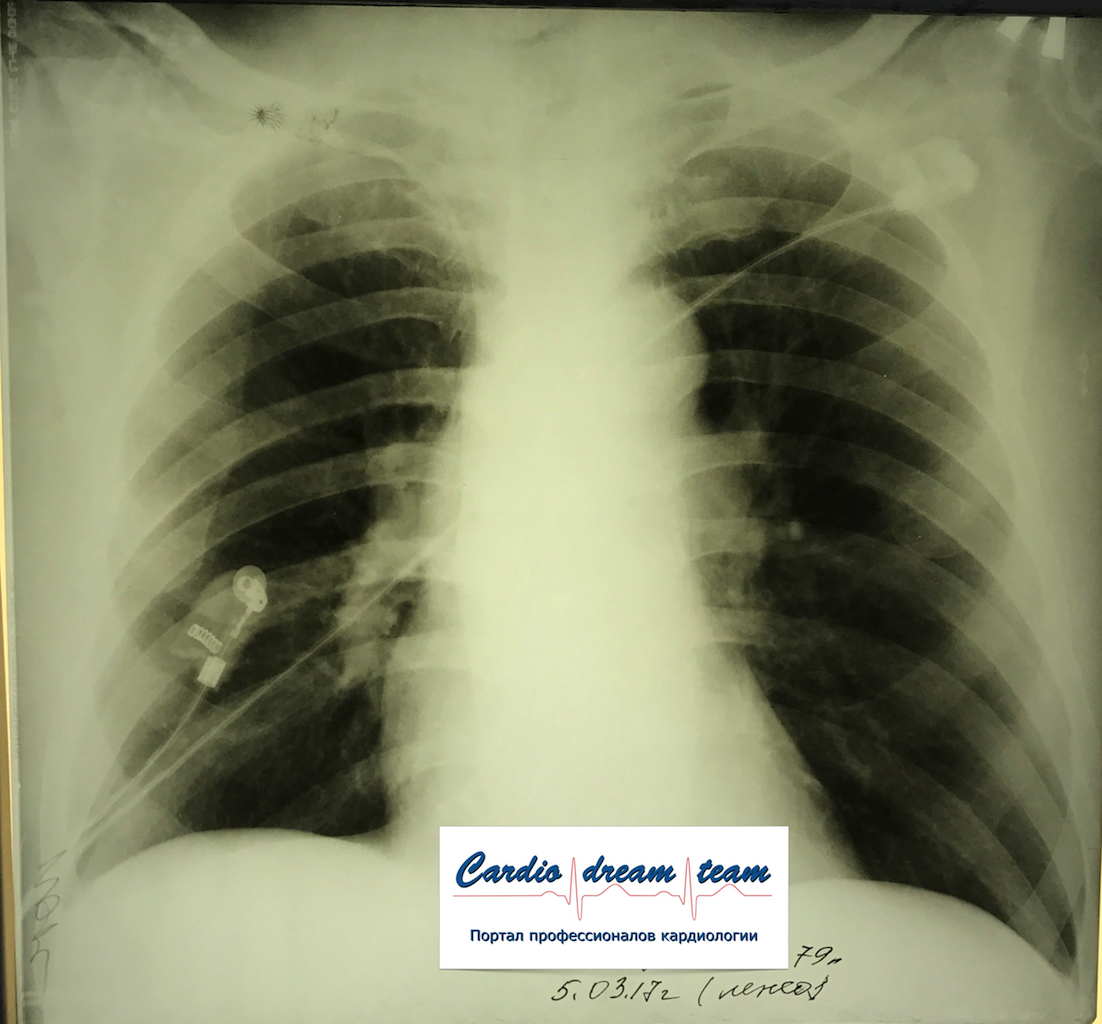

Не обсуждалась Дата 23-ИЮЛ-15 ОПИСАНИЕ: Проведена рентгенография органов грудной клетки в прямой проекции, положение лежа, условия ПИТ Легочные поля: неравномерно прозрачны за счет сосудистого обогащения, в базальных отделах с обеих сторон, отмечается сгущение легочного рисунка, за счет гиповентиляции, в плевральных полостях жидкость Легочный рисунок: Изменен по смешанному типу: обогащен за счет сосудистого компонента, деформирован за счет склероза. Корни: бесструктурны, расширены за счет сосудистого компонента, обогащены Синусы: определяется наличие жидкости по линии 5 ребра Сердце: широко лежит на диафрагме отмечается расширение границ сердечной тени влево, вправо экг-электроды. ЗАКЛЮЧЕНИЕ: Рентген-признаки 2-х стороннего гидроторакса с гиповентиляцией базальных сегментов.. Признаки застоя по МКК 2 степени (умеренно выраженный). Пневмосклероз. Р-признаки гипертрофии левого желудочка сердца. Склероз аорты.